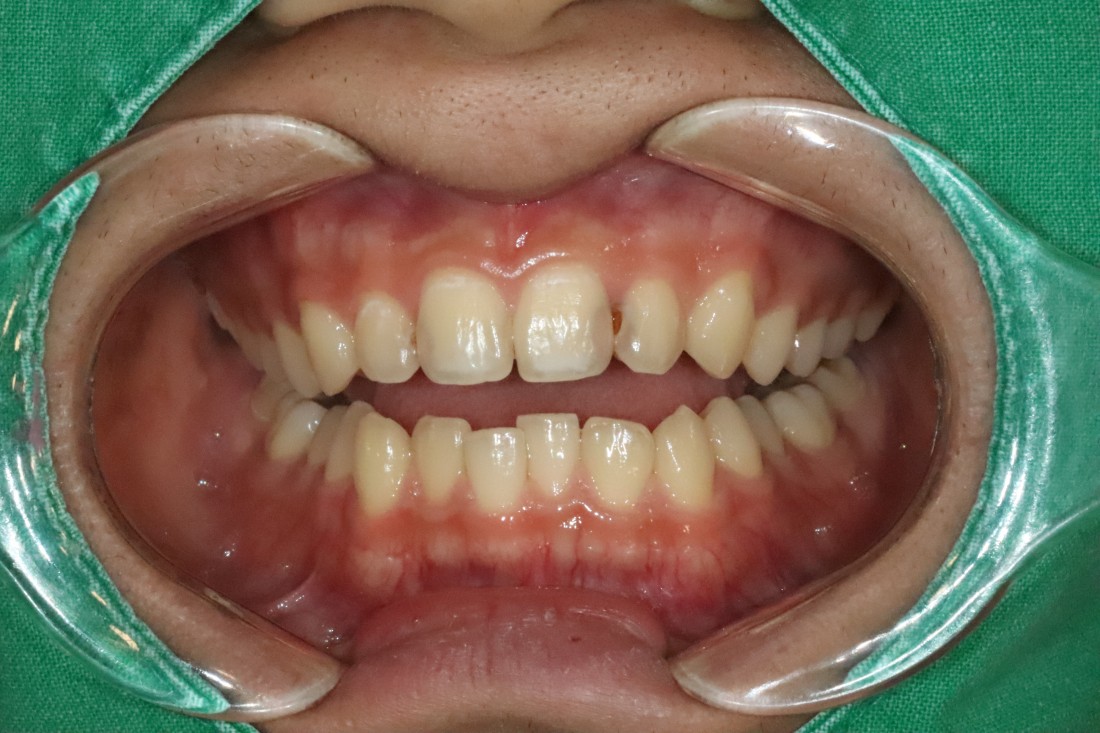

광주 라미네이트 치과에 방문해주신

40대 여성 고객님의 케이스입니다.

앞니 사이에 충치 치료로

검게 변색된 부분이

오랜시간 컴플렉스로 작용하셔서

환하게 웃지를 못했다고 하셨어요.

앞니를 자세히 보시면

색도 변색이 되었을 뿐만 아니라,

사이 충치로 인해 구멍이 생겨있어

세련된 첫인상에 부정적 영향을 끼치는데요.

광주 라미네이트 치과에서

앞니 라미네이트 진료를 통하여

환한 미소를 완성시켜드렸습니다.